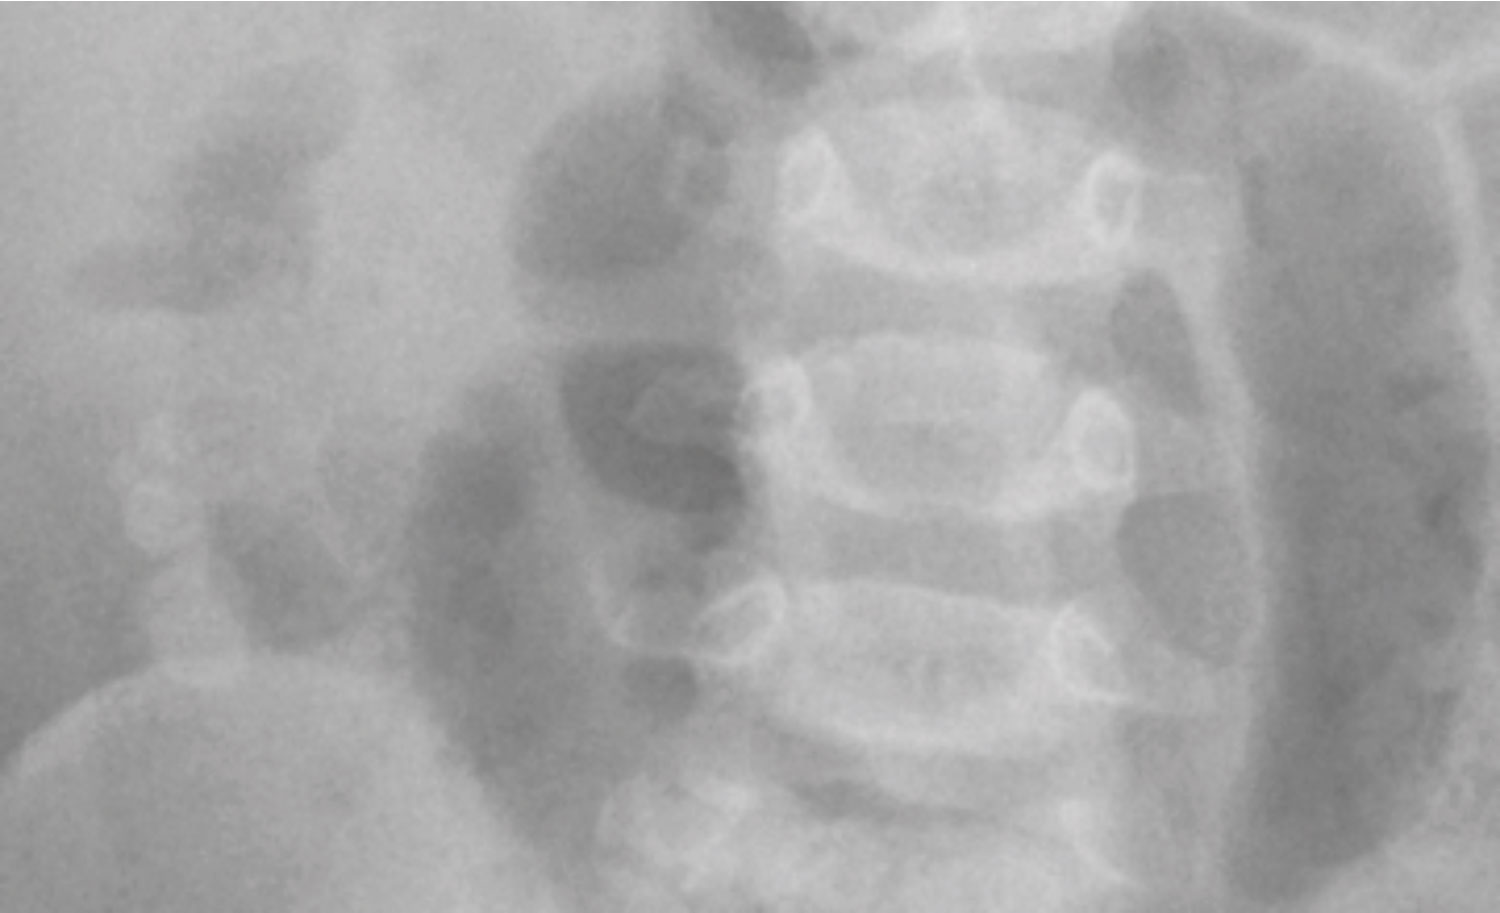

X-ray abdomen showed centrally situated, dilated, air filled small bowel loops. There were visible areas of calcification in RIF on plain film with provisional diagnosis of faecolith, confirmed later by ultrasound and laparoscopy.